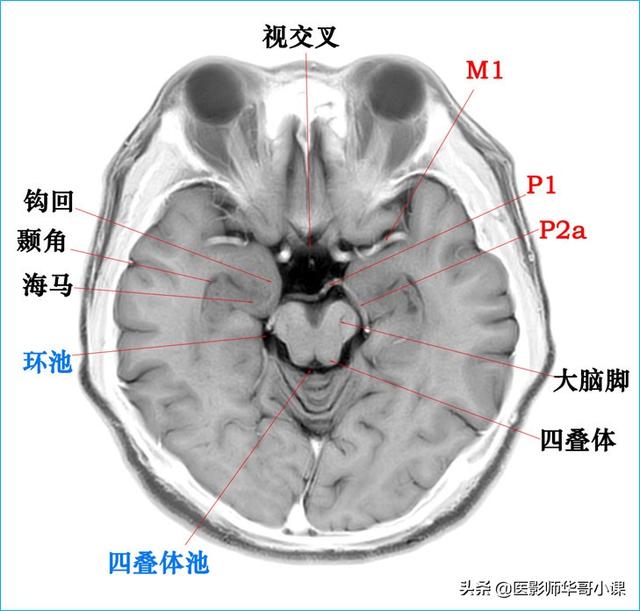

颅脑主要包括大脑、小脑、脑干、间脑,其中大脑又称为端脑,是人体的司令部,管辖人体的躯体活动、精神活动以及感觉行为等;脑干和小脑位于后颅窝的位置,脑干自上而下分为中脑、脑桥、延髓,脑干又称为生命中枢,对人体非常重要,因为脑干具有管辖呼吸和循环的初级生命中枢。其中大脑分为5个脑叶,分别是额叶、顶叶、颞叶、枕叶以及内侧面的岛叶。间脑分为上丘脑、下丘脑、后丘脑、背侧丘脑和底丘脑,背侧丘脑是一个重要的结构,是感觉传导路的重要中继站。颅脑包括颅骨和颅骨内的脑组织。颅骨由顶骨,颞骨,枕骨,额骨,以及颅底骨构成。颅骨构成的颅腔主要作用是保护脑组织。颅内的脑组织主要包括大脑,小脑,脑干。表面覆盖有软脑膜和硬脑膜,大脑分为左右两侧大脑半球,根据解剖位置又分为颞叶,枕叶,顶叶,额叶,各脑叶功能不尽相同。小脑也分左右半球。脑干分为延髓,脑桥和中脑三部分。